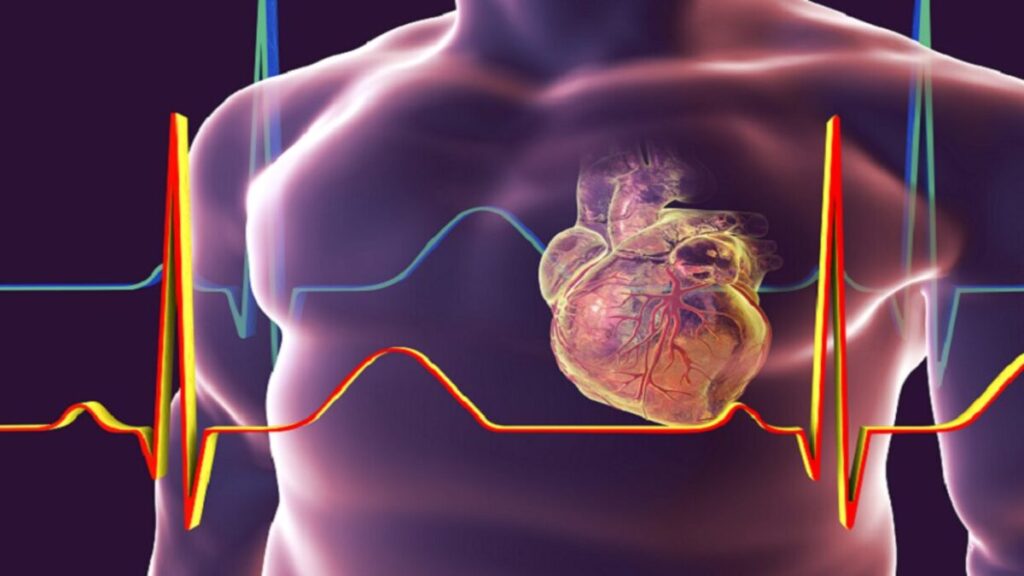

حذر خبراء الصحة من أن تخطي تناول الوجبات أثناء ساعات العمل يحمل مخاطر جدية، حيث يؤدي إلى تقلبات في مستويات السكر في الدم وزيادة ضغط القلب.

ووفقًا لتقرير نشره موقع “هندوستان تايمز”، فإن هذا السلوك الشائع في بيئة العمل السريعة يُشكل محفزًا لتأثيرات سلبية على التمثيل الغذائي والأوعية الدموية، مما يُبرز أهمية الالتزام بوجبات منتظمة ومتوازنة للحفاظ على صحة القلب.

وأوضح الدكتور ديكسيت جارج، استشاري أمراض القلب التداخلية في مستشفى مانيبال بالهند، أن تخطي الوجبات يفعّل استجابة تعويضية في الجهاز العصبي الذاتي، ما يؤدي إلى تحلل الدهون والبروتين لإنتاج الطاقة.

وأضاف أن ذلك يُسبب “ارتفاع ضغط الدم نتيجة زيادة انقباض عضلة القلب وتغيرات الأوعية الدقيقة”.

وأشار الدكتور إلى أن هذا السلوك، على المدى الطويل، قد يؤدي إلى تكوين أنسجة ليفية ووفاة خلايا القلب، كما يساهم في مقاومة الأنسولين، وهو عامل رئيس في تطور مرض السكري واضطرابات التمثيل الغذائي التي تزيد من خطر الإصابة بأمراض القلب.

وأضاف أن ارتفاع هرمون الكورتيزول الناتج عن فترات الانقطاع الطويلة عن الطعام يسهم في ارتفاع ضغط الدم والإصابة بأمراض القلب.